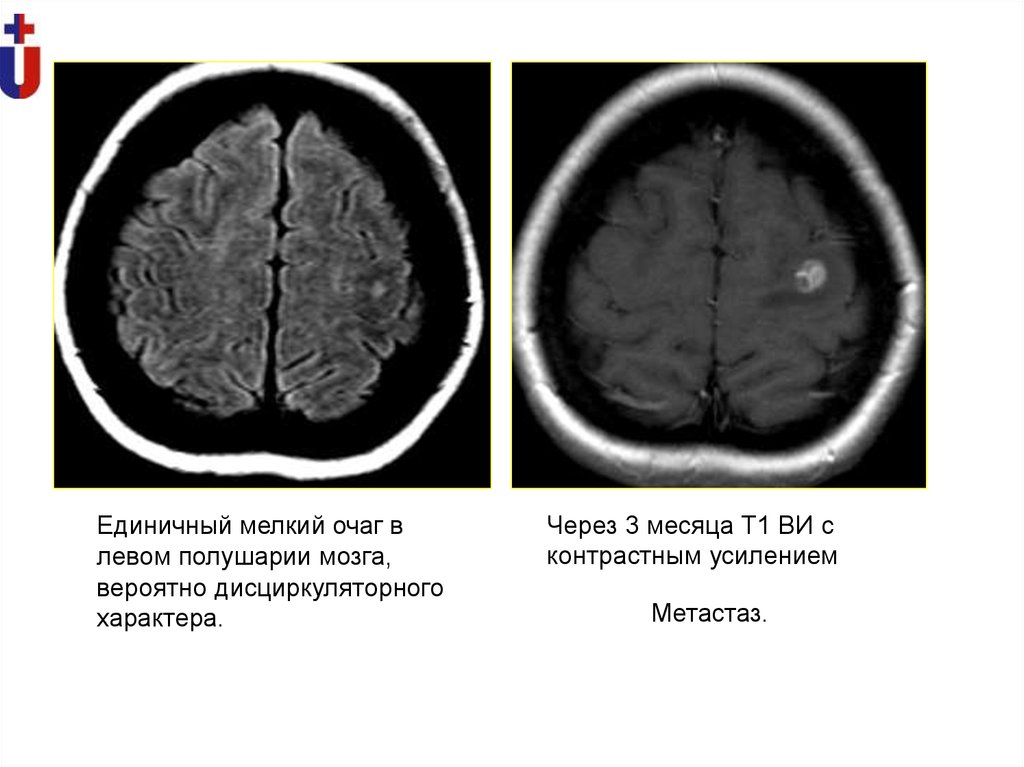

Единичный мелкий очаг в

левом полушарии мозга,

вероятно дисциркуляторного

характера.

Через 3 месяца Т1 ВИ с

контрастным усилением

Метастаз.